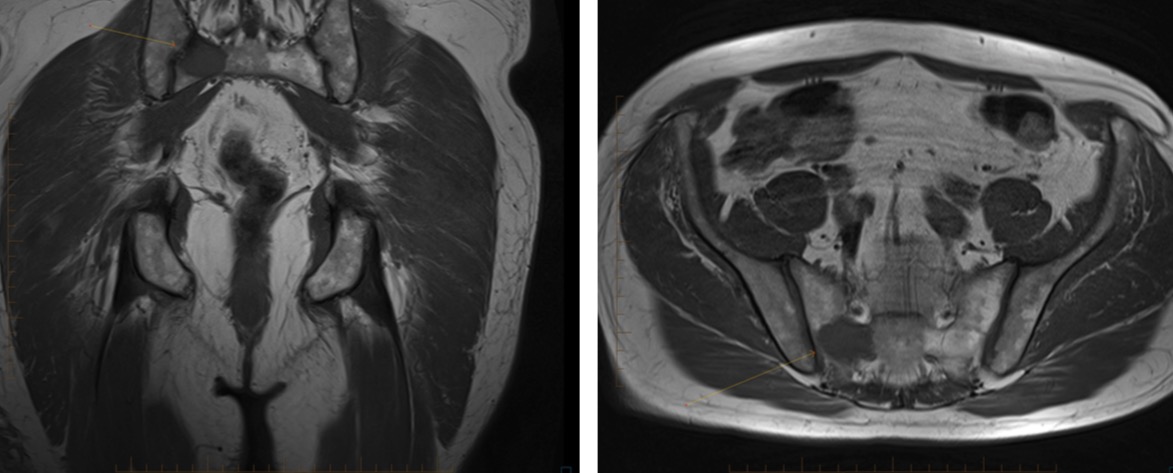

70 male prostate CA with groin mass

FEMORAL ARTERY LEIOMYOSARCOMA WITH BONE METASTASES.

• METASTASES AT PRESENTATION ARE COMMON - APPROX 50%